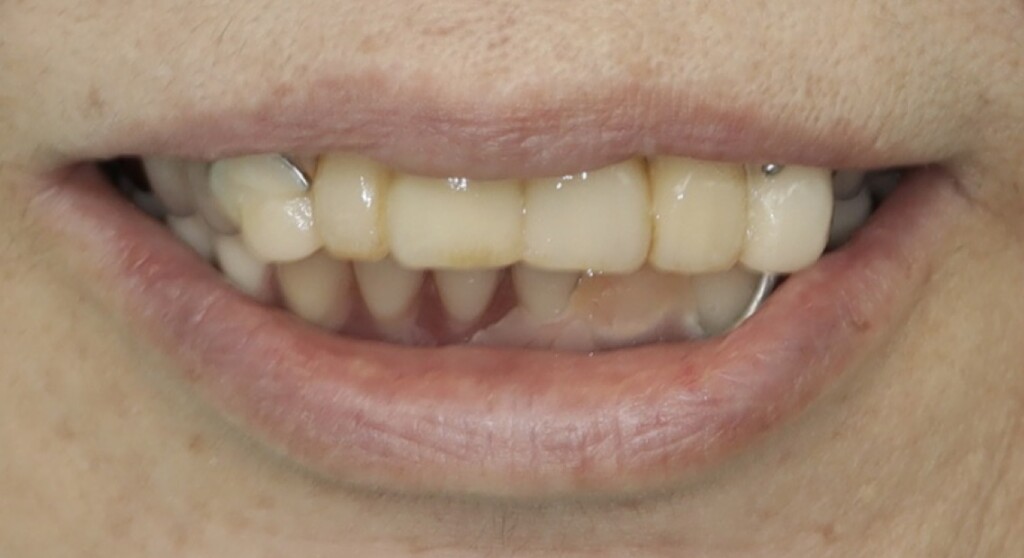

最終精密義歯仮合わせ時

装着された仮歯と仮の入れ歯

乱れた噛み合わせの平面

修正して整えた噛み合わせの平面

いきなり最終的な歯や入れ歯を作るのではなく、段階的に治療を進めていきました。

まずは仮歯と仮の入れ歯を用いて、乱れていた見た目や噛み合わせの平面を整えました。そのうえで、その状態が実際にお口の中で無理なく機能するか、違和感なく順応できるかを確認し、残っている歯の状態を評価しました。さらに、ブリッジやクラウンによる修復が可能かどうかについても、慎重に判断を行いました。残っている歯はいずれも神経の処置がされている歯でしたが、根管内の状態に問題が認められたため、再度根管治療を行っています。具体的には、仮歯を外して根管治療を行い、治療後に土台を立て、再び仮歯を仮止めで装着する、という工程を繰り返し行いました。